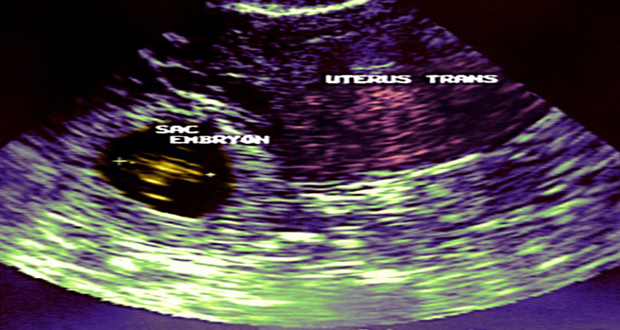

أصبحت امرأة هندية صاحبة أطول فترة حمل خارج الرحم بعد أن أزال الأطباء هيكل جنين بقي داخل بطنها نحو أربعة عقود.

وذكرت أ ف ب أن جويتي كومار وهي من ولاية ماديا براديش في وسط الهند حملت سنة 1978 عندما كان عمرها 24 عاماً وأخبرها آنذاك الأطباء أن ابنها لديه فرص قليلة للحياة بعد أن وجدوا أنه ينمو خارج رحمها لكن بسبب خوفها من العملية الجراحية فرت الشابة وسعت للحصول على علاج للآلام من عيادة صغيرة.

وبعد عدة أشهر عندما هدأت الآلام اعتقدت كومار أن المشكلة عولجت لكن بعد 38 عاماً بدأت المرأة تعاني من آلام دائمة في معدتها فأجرى لها فريق من الجراحين عملية لإزالة عظام ابنها الذي لم يولد بعد.

وتم بالفعل إزالة كتلة من داخل بطن السيدة هي هيكل طفل كان قد تشكل بين الرحم والأمعاء والمثانة.